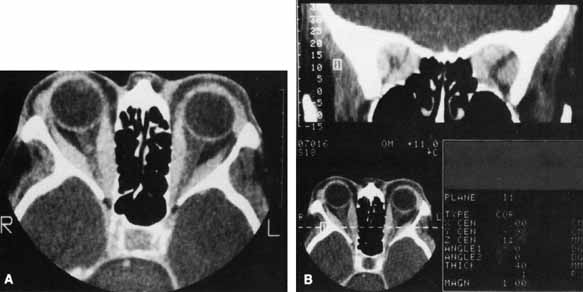

Most cases of optic neuropathy are due to compression of the optic nerve by the enlarged extraocular muscles at the orbital apex (Fig. 5). Patients with compressive optic neuropathy have a more symmetric involvement of the extraocular muscles as compared with most patients with thyroid disease.65 Although patients with optic neuropathy usually have proptosis, optic neuropathy can occur without significant proptosis in patients whose orbital septum efficiently limits anterior globe displacement, despite increased retrobulbar pressure. Very rarely, optic neuropathy can occur without significant muscle enlargement. In these cases, it is postulated that a short optic nerve is being stretched or the optic nerve is being compressed by surrounding orbital fat.49 These cases are so rare that optic neuropathy in the absence of muscle enlargement or proptosis should be investigated thoroughly to rule out other etiologies.

Fig. 5 A. Axial CT scan of a patient with compressive optic neuropathy. Note that position of globe shows only mild proptosis, and orbital fat is not increased in volume. The posterior portion of the extraocular muscles is markedly enlarged, compressing the optic nerve. B. Coronal CT scan of the orbital apex in the same patient clearly shows displacement of orbital fat by enlarged muscles. The apex is “crowded,” consistent with clinical findings of optic neuropathy.

CT is not necessary in most patients who present with a clinical picture and supporting laboratory evidence of Graves' disease. It is, however, indicated when optic neuropathy is suspected, before orbital decompression, to examine the anatomic relationship of the orbit to both the sinus cavities and the cribriform plate, in patients with atypical proptosis or motility disturbances; or instead of ultrasonography to detect early thyroid orbitopathy in patients with equivocal results of laboratory tests. Like ultrasonography, CT allows reliable identification of even minimal enlargement of the recti muscles.40 Of those patients with clinical unilateral thyroid orbitopathy, CT will detect subclinical enlargement of the extraocular muscles on the contralateral side in 50%.75

The most characteristic CT finding in thyroid orbitopathy is enlargement of the extraocular muscles, which is usually bilateral and symmetric and has a fusiform configuration, with sharply defined borders and sparing of the tendinous insertions. Atypical cases with tendon involvement and blurred muscle margins have been described.75

The pattern of muscle enlargement on CT parallels that seen clinically. The inferior rectus is the most commonly involved, followed by the medial rectus, superior rectus, and lateral rectus. Other findings include proptosis and anterior prolapse of the orbital septum due to excessive orbital fat and muscle swelling (see Fig. 4).76 Also, lacrimal gland enlargement and bone remodeling without erosion can occur.75 Patients at risk for developing optic neuropathy may also have severe apical crowding, a dilated superior ophthalmic vein, and anterior displacement of the lacrimal gland.68 Of these, apical crowding is the most sensitive indicator for the presence of optic neuropathy (Fig. 5A).56 Both axial and coronal CT cuts should be obtained; the coronal plane is needed to assess the enlargement of the extraocular muscles at the apex (see Fig. 5B).